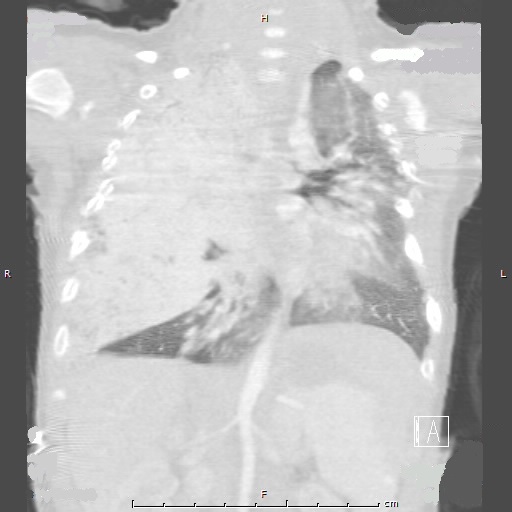

Diagnostic imaging. A chest radiograph showed near opacification of the right lung with a slight leftward mediastinal shift. Contrast enhanced computed tomography (CT) of the chest showed a large vascular mass in the right hemithorax and upper abdomen (Figure 1). Magnetic resonance imaging (MRI) of the chest and abdomen revealed 2 left upper quadrant abdominal masses. The pulmonary mass was biopsied and results eventually confirmed it to be an infantile hemangioma.

Figure 1: Computed tomography of the chest with contrast performed at 2 months of age shows enhancing masses in the right lung and upper abdomen.